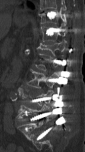

Eski Lomber Stabilizasyon Sistemi Altında Kırık (2)

Ağustos 2023